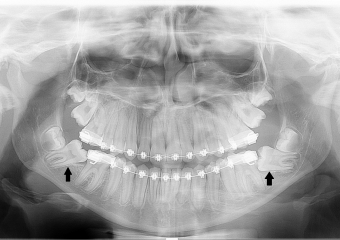

Rx Panorâmico - Pré cirúrgico, com os elementos 37 e 47 impactados - Clínica Cliniface

Rx Panorâmico - Pré cirúrgico, com os elementos 37 e 47 impactados